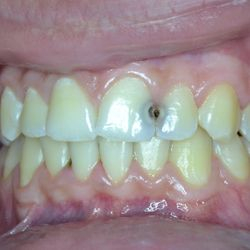

Η νεαρή αυτή ασθενής μας είχε ολοκληρώσει παλαιότερη ορθοδοντική θεραπεία, η οποία είχε οδηγήσει σε νέκρωση τον άνω δεξιό κεντρικό και πλάγιο τομέα.

Τα δόντια αυτά είχαν απονευρωθεί στο παρελθόν και είχαν μαυρίσει.

Τοποθετήθηκαν άξονες υαλονημάτων (ParaPost FiberWhite/Coltene) για ενίσχυση των ριζών και στη συνέχεια χτίστηκαν όψεις ρητίνης (Herculite XVR Ultra/Kerr) για να διορθωθεί η δυσχρωμία τους.